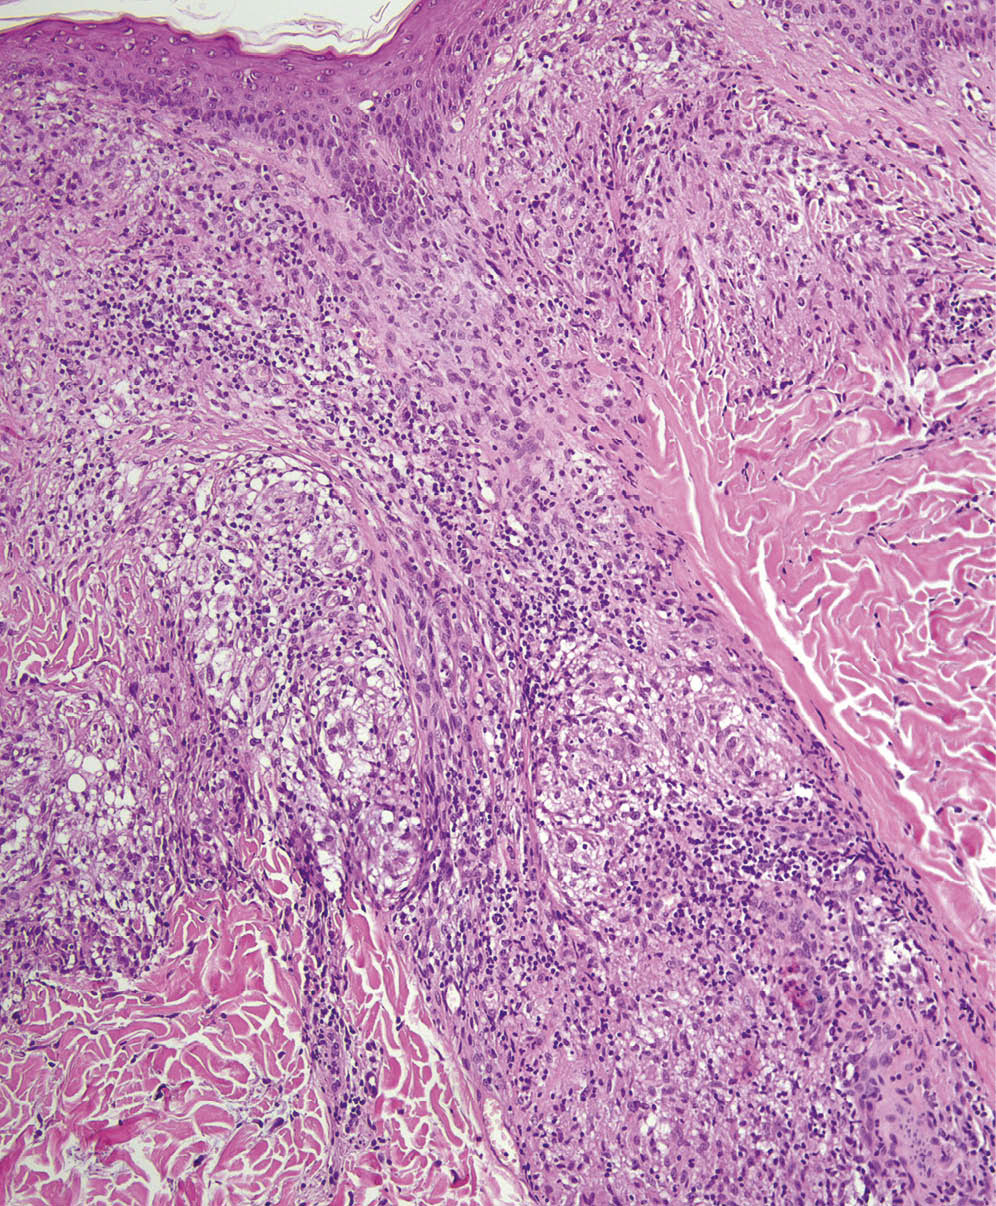

При гистологическом исследовании высыпаний при саркоидозе обычно обнаруживаются эпителиоидноклеточные гранулемы в дерме или подкожной жировой клетчатке, содержащие эпителиоидные клетки, гистиоциты и гигантские клетки, по периферии гранулем могут располагаться лимфоциты в небольшом количестве; в 20% случаев в центре гранулемы отмечается фибриноидный некроз [16]. У нашей пациентки при гистологическом исследовании определялись саркоидные гранулемы, расположенные в дерме вокруг инфундибулярной части волосяных фолликулов, состоящие из эпителиоидных и гигантских клеток (рис. 2–4).

Рис. 2. Волосяной фолликул практически на всем протяжении окружен сливающимися гранулемами саркоидного типа

Рис. 3. Саркоидные гранулемы состоят преимущественно из эпителиоидных клеток

Рис. 4. Саркоидная гранулема прилежит к фолликулярному эпителию у места впадения протока сальной железы в фолликул